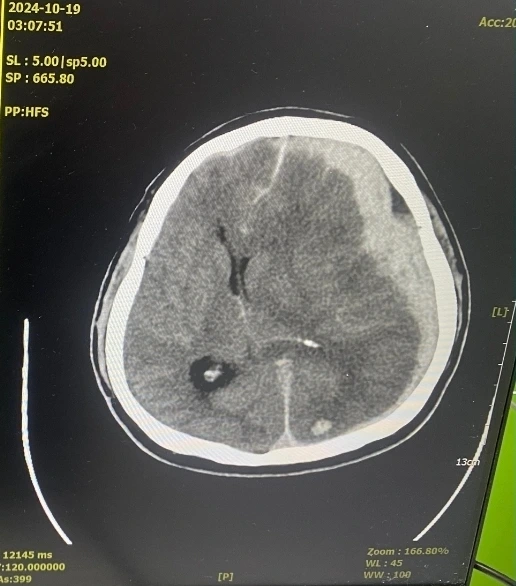

나는 밖에서 엄마와 기다리다 응급실에서 울면서 전화한 남동생 콜을 받고 의사로부터 뇌 CT 결과를 같이 전해 들었다.

이미 뇌에 피가 너무 많이 고여 뇌손상이 심해져 있는 상태이고 마음의 준비까지 해야 한다는 청천벽력 같은 소리였다.

​의사는 덧붙였다.

수술을 시도할 수는 있지만, 아빠의 연세와 고혈압, 협심증 같은 지병을 고려할 때 수술 자체를 견뎌낼 수 있을지 장담하기 어렵다고. 그러니 수술 여부를 지금 당장 결정해 달라고 우리를 재촉했다.